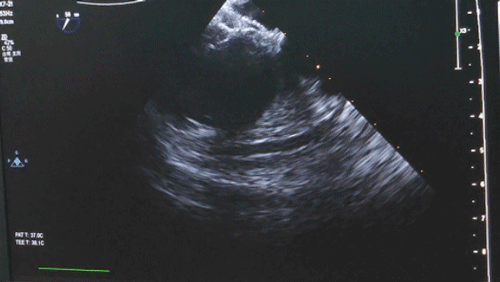

穿刺右側股靜脈,置入動脈鞘管,靜脈注射肝素80U/kg。經動脈鞘管送入6F右心導管及泥鰍導絲,在超聲引導下將導管及導絲送過未閉卵圓孔,交換加硬導絲,退出導管及動脈鞘管。

沿加硬導絲將9F輸送鞘送至左心房,退出導絲及輸送鞘內芯后,在超聲引導下送入1824PFO封堵器進行封堵。先釋放左盤面,整體回撤,緊貼房間隔,后釋放右盤面,進行推拉試驗,超聲在主動脈短軸切面、四腔心切面確認封堵器對二尖瓣等周圍組織無影響,位置及形態良好后釋放封堵器。撤出長鞘、縫合穿刺點后壓迫止血,加壓繃帶包扎,手術結束。

導管嘗試過隔

鞘管到達左心房